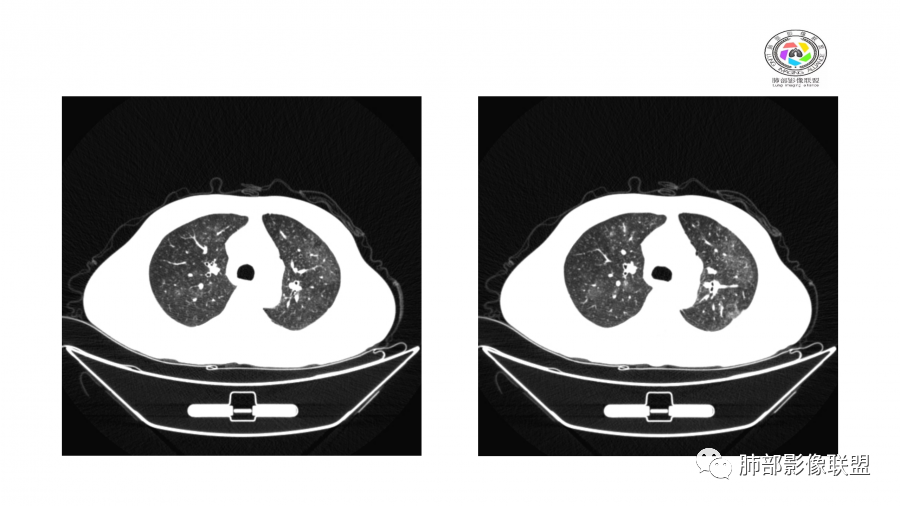

双肺多发实变及磨玻璃影,边界欠清,部分可见小叶间隔增厚,支气管穿行病灶内,多次随访复查,部分有吸收又似有新发,双侧纵隔淋巴结肿大,临床:男性49岁,肾功能异常,考虑GPA,OP

中年男性,肌酐高,两肺外周分布为主多发结节及斑片影,周围有晕,短期复查变化快,游走性,考虑血管炎,鉴别真菌感染

影像:双肺多发结节丶片影,短期内右下消失,

cRp丶PcT上升,wBC正常,应该合并感染

整体考虑:ANCA相关性血管炎,既发肾病丶肺OP样改变。

诊断考虑:1.综合患者资料,初次治疗4天后影像即有改善,考虑原发高血压存在?高血压性肾病,肾源性肺水肿。2.高血压为肾衰并发症,肾小囊肿、小结石不足以解释肾衰,ANCA血管炎要考虑,鉴别PVOD、PCH等。3.血像不高,肺部不典型病原体感染待排,病毒、衣原体等,进一步完善相关检查。

王秀仙: